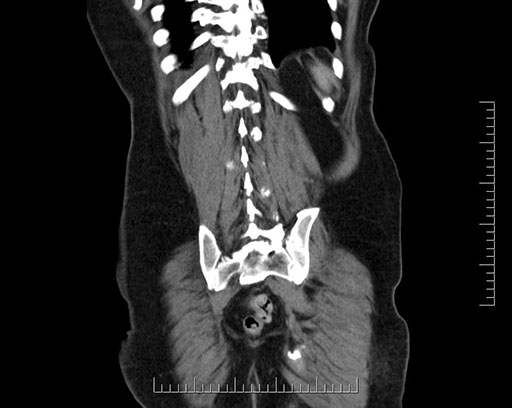

Imaging Analysis

Look through the patient's CT scan to identify any areas of concern for the necessary procedure.

Based on your CT findings, which issue(s) would give reason for "planned slowing down moment(s)" in this case?

Considering a standard Whipple procedure, what step(s) of the operation would you do differently in this case?